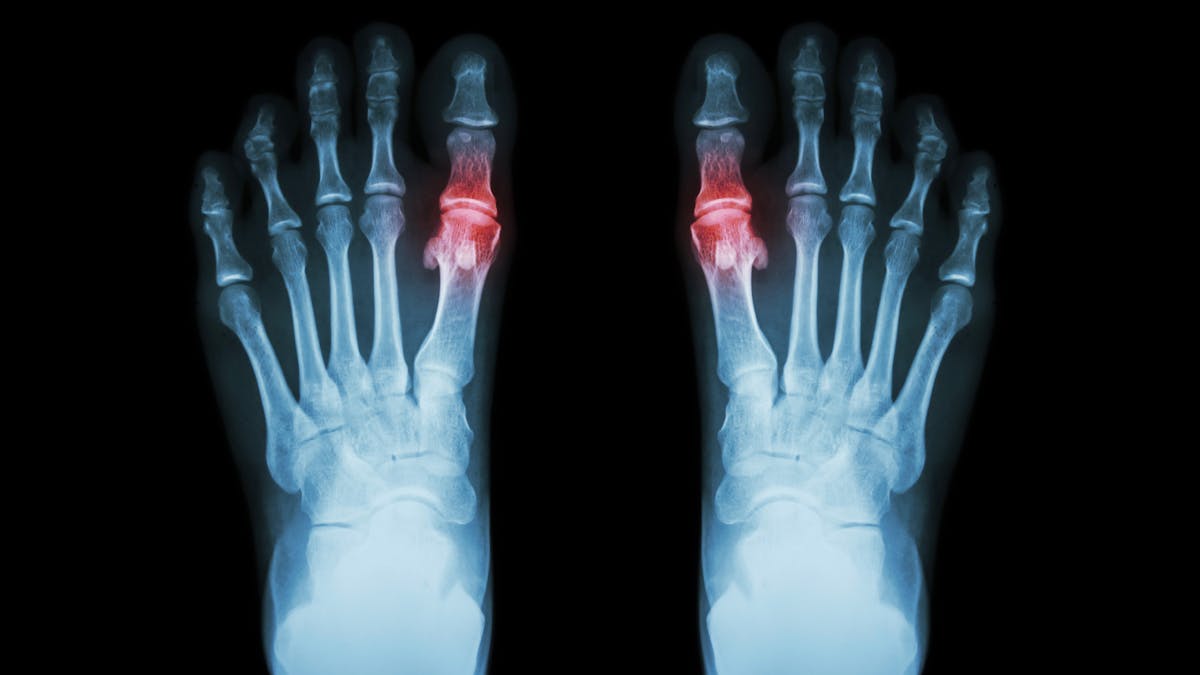

¿Tienen cabida los almidones en las dietas cetogénicas? ¿Podemos culpar a la cetosis del rebrote de gota?

| Cardiopatía (14) | Gota (2) | Trastorno bipolar (8) |